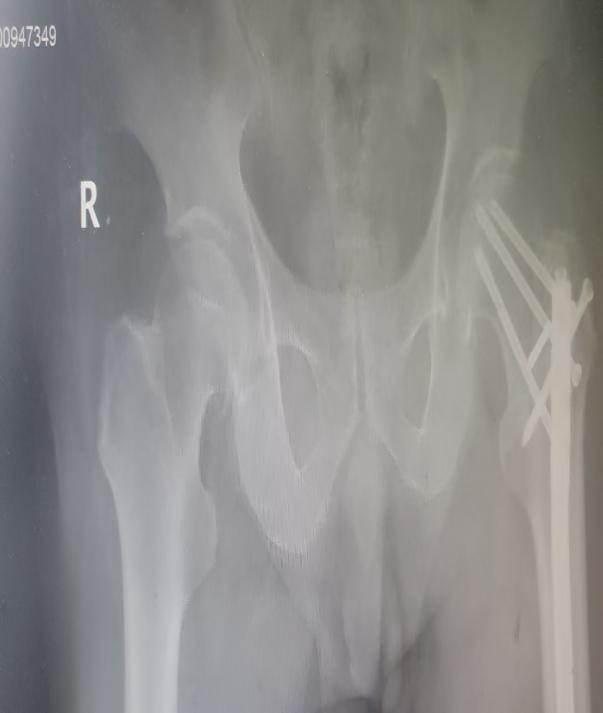

患者胡先生因左侧髋部疼痛不适入院,经检查确诊为左侧股骨颈基底部骨折,同时合并左股骨骨干骨折术后骨不连、心房颤动及高血压病3级(极高危)。更棘手的是,患者30年前曾因股骨干骨折接受髓内钉内固定术,此次骨折位置恰好位于髓内钉近端且骨不连,内固定装置无法取出,让传统治疗方案彻底陷入绝境。

患者术前X线图